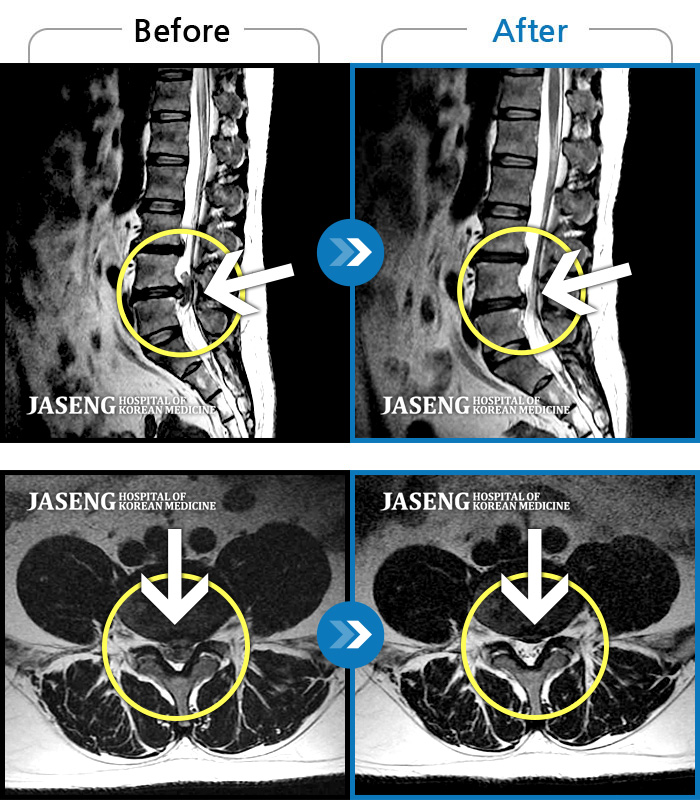

허리디스크

보라매 · 강준규 원장

좌측 다리 뒤쪽으로 통증이 심해서 걸어다니기 힘들어요

촬영시기

2024.01.30 ~ 2024.07.09